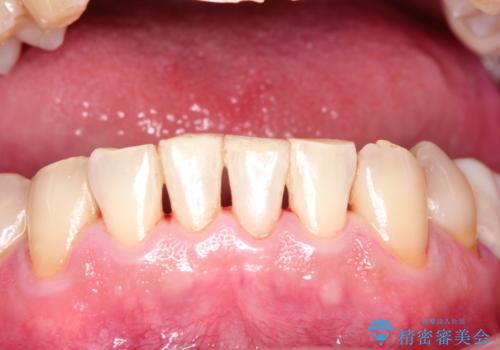

- 日頃の積み重なった茶渋・着色をエアフローにてクリーニングしました。

歯の表面に着色が付いて黄ばんで見えることがあるため、PMTCを行うとご自身の歯本来の色味にすることができます。

定期的にPMTCを行うことで綺麗な状態を維持することができます。